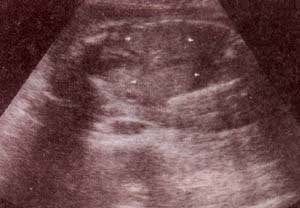

fig. 83. – (a). displasia renal infantil. potter tipo i. 22 semanas. corte longitudinal. los riñones están compuestos por múltiples microquístes que le el aspecto ecográfico hiperecogénico en “esponja” |

fig. 83. – (b). 22 semanas. corte coronal. los riñones aumentados de tamaño estan ocupando prácticamente todo el abdomen |